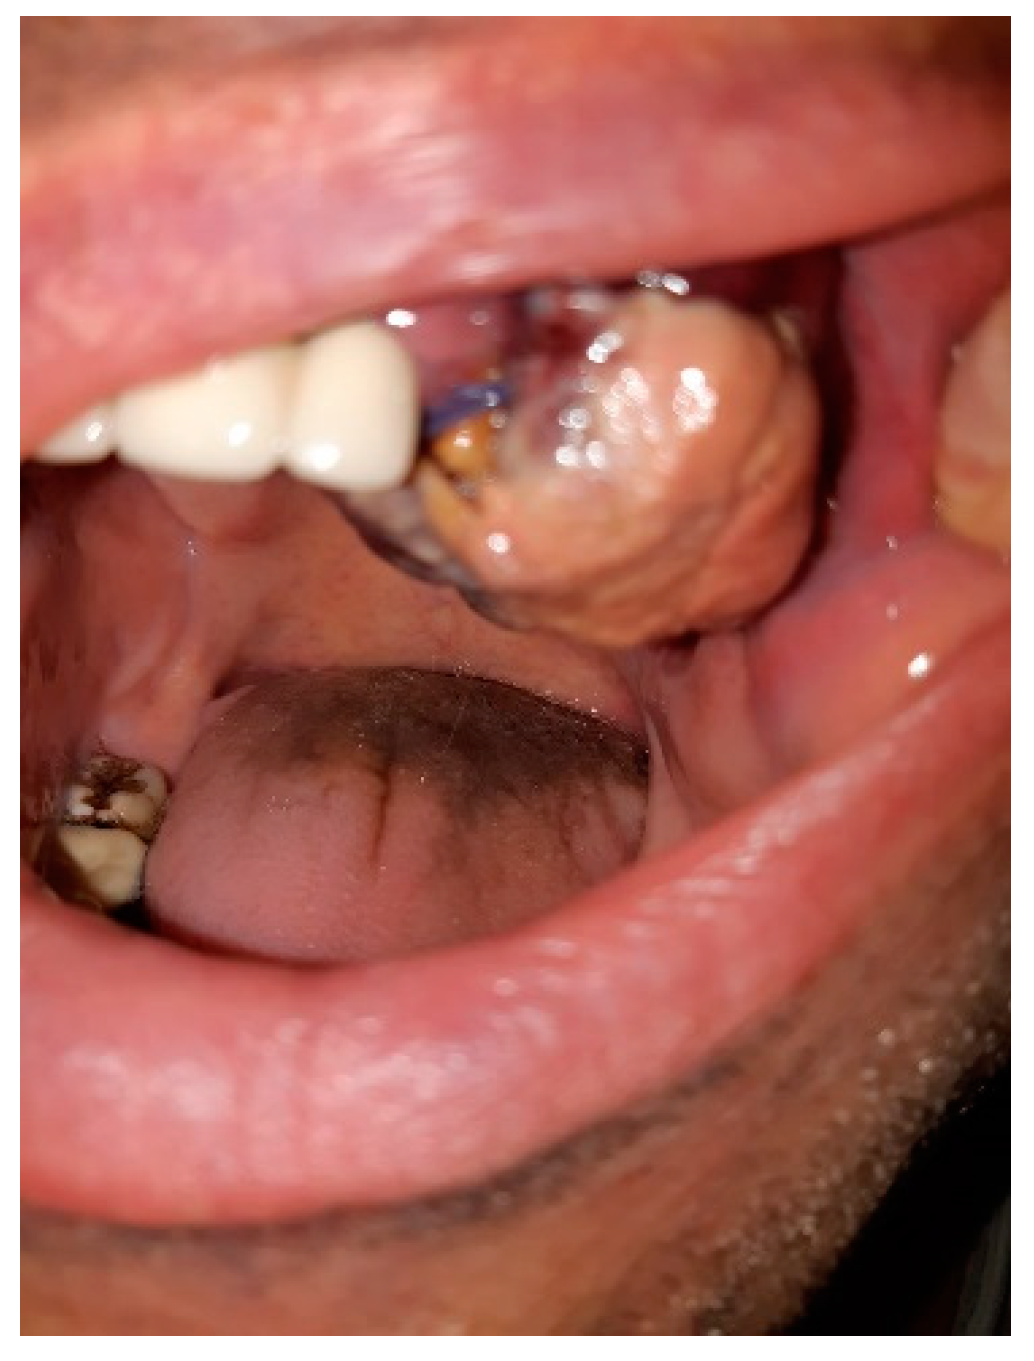

2. Case Presentation

| COVID-19 | Ulcer-vegetative tumor lesion in the oral cavity HIV | Plasmablastic lymphoma Start ART (genvoya) | Dose-adjusted-EPOCH chemotherapy (six cures) | Radiotherapy | PETT–CT favorable evolution |